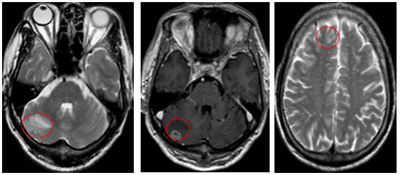

Ca lâm sàng: Chẩn đoán ung thư tuyến giáp di căn não tại Trung tâm Y học hạt nhân và Ung bướu, bệnh viện Bạch Mai

Ung thư tuyến giáp (UTTG) là loại ung thư phổ biến nhất trong các ung thư của hệ thống tuyến nội tiết, với tỷ lệ mắc có xu hướng gia tăng trong những năm gần đây. Theo GLOBOCAN 2022, UTTG đứng hàng...